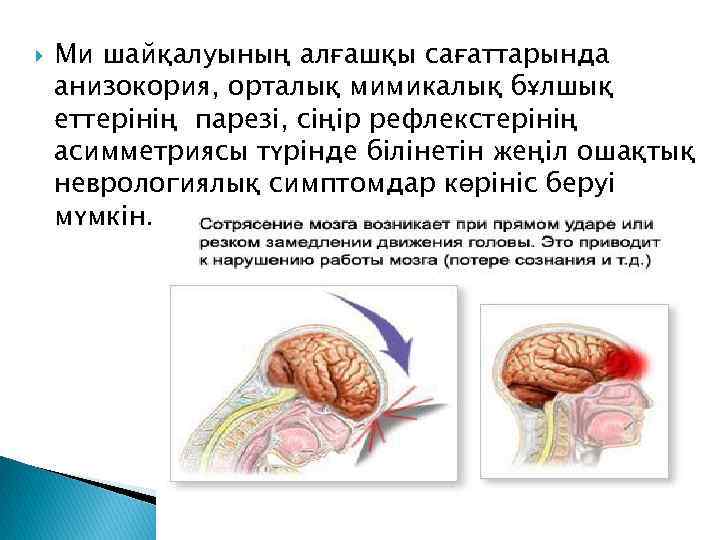

Ми шайқалуының алғашқы сағаттарында анизокория, орталық мимикалық бұлшық еттерінің парезі, сіңір рефлекстерінің асимметриясы түрінде білінетін жеңіл ошақтық неврологиялық симптомдар көрініс беруі мүмкін.